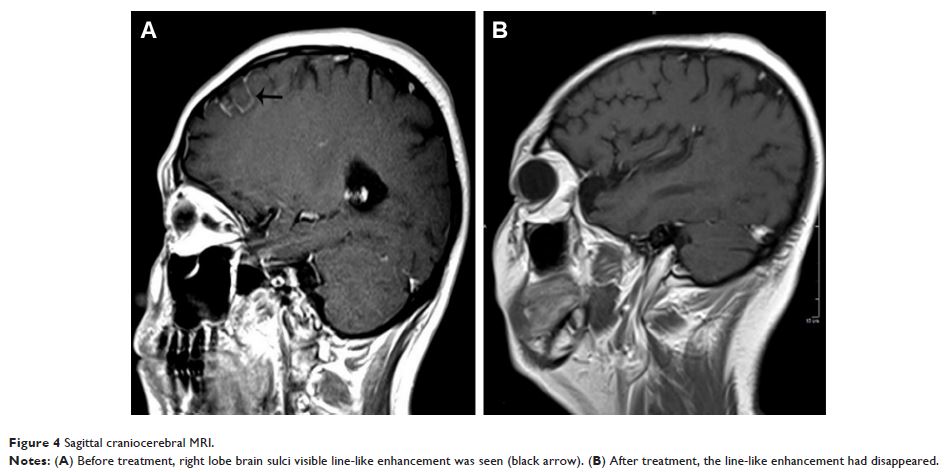

- 作者:Xiong Xiao, Hao Ren, Nan Ji, Fang Luo

- 期刊:Journal of Pain Research